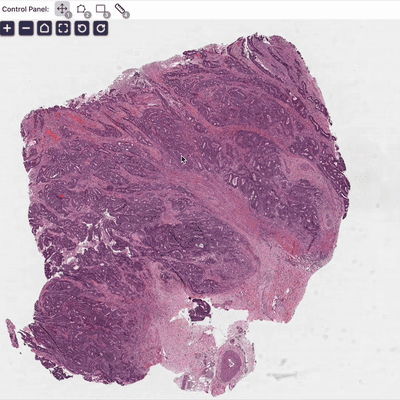

1. Foundation Model for Pathology

Pathology is medicine's ground truth. We train AI models with vision, language, and knowledge to improve machine understanding of pathology.

A visual–language foundation model for pathology image analysis using medical Twitter

Zhi Huang†, Federico Bianchi†, Mert Yuksekgonul, Thomas J. Montine, James Zou (†: Equal contribution)

Nature Medicine (2023), cover article

✨ Checkout our OpenPath, a vision-language dataset for pathology at here.